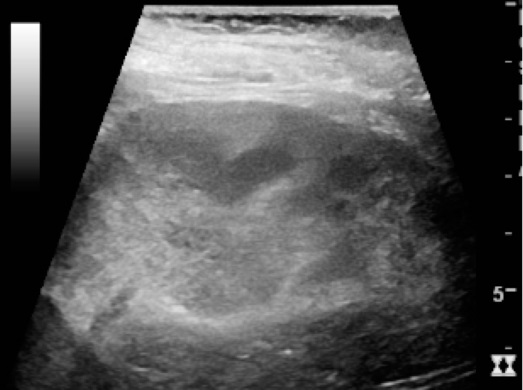

신우신염을 나타내는 초음파 소견은 신장 비대, 신동 또는 실질의 부종, 출혈, 피질수질 경계 소실, 농양 형성 또는 도플러 초음파에서 혈류 저하 영역이다.[21] 그러나 신우신염 환자의 20~24%에서만 초음파 소견이 관찰된다.[21]